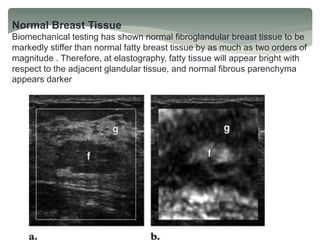

Normal Breast Tissue

Biomechanical testing has shown normal fibroglandular breast tissue to be

markedly stiffer than normal fatty breast tissue by as much as two orders of

magnitude . Therefore, at elastography, fatty tissue will appear bright with

respect to the adjacent glandular tissue, and normal fibrous parenchyma

appears darker

(a) B-mode US image of the breast shows that a lobule of normal fatty tissue (f) is

hypoechoic with respect to the surrounding glandular tissue (g).

(b) US elastogram shows that the fatty tissue (f) surrounded by dense breast

tissue appears bright because it is appreciably “softer” than the surrounding

glandular tissue (g).